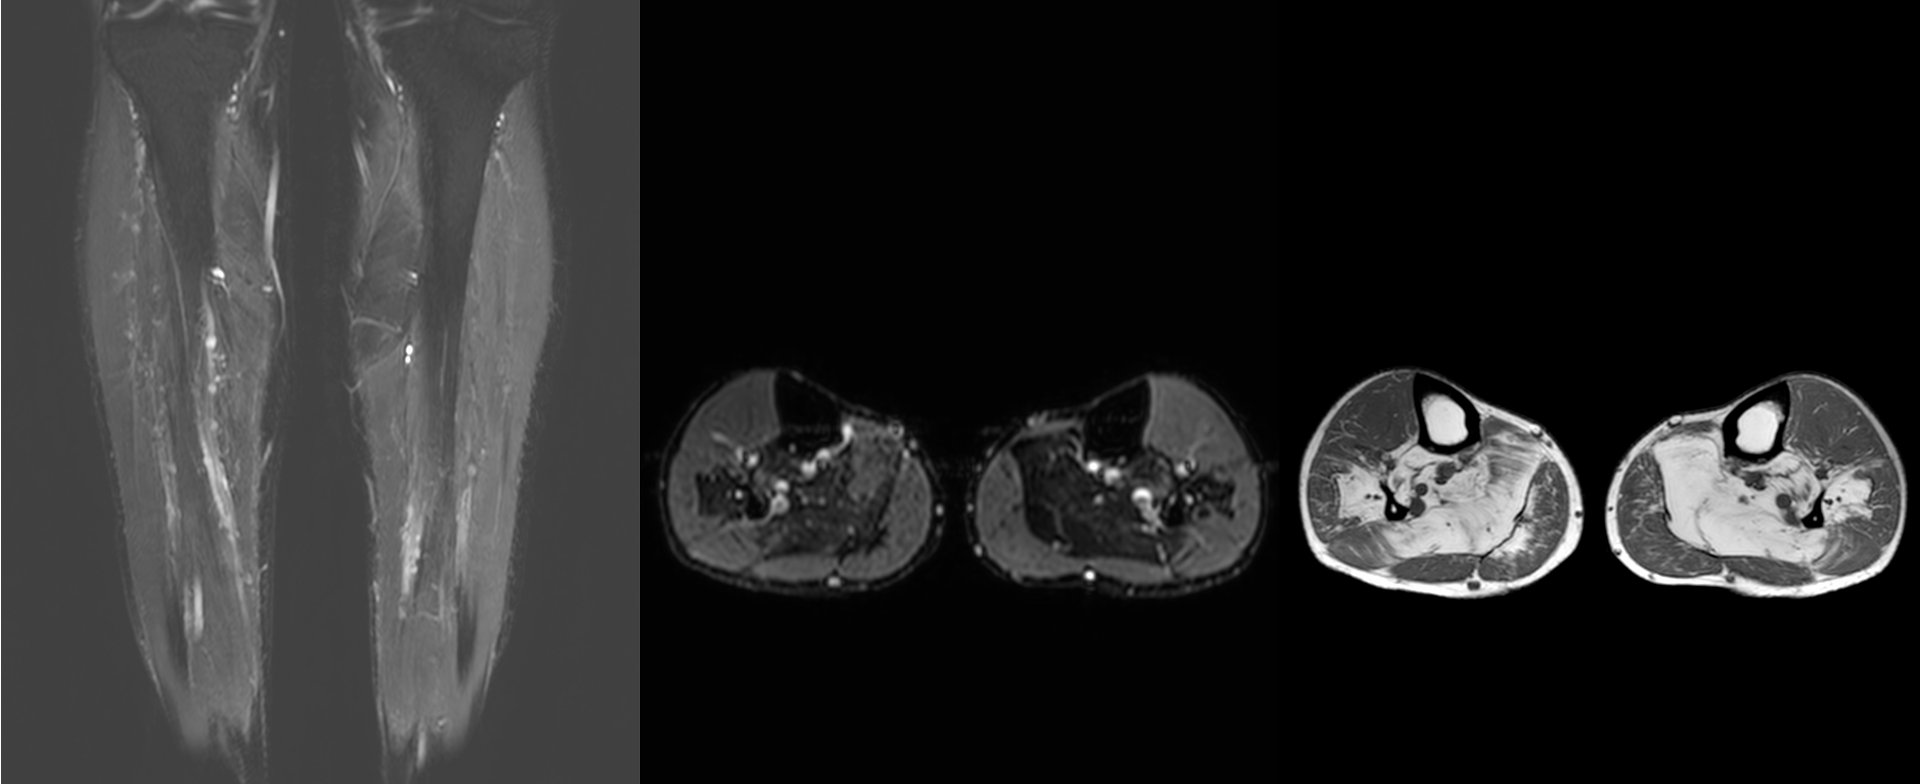

Case 61: Dermatomyositis and the Myositis Protocol MRI

55-years old with dermatomyositis

55-years old diagnosed to have dermatomyositis, referred for a myositis protocol MRI.